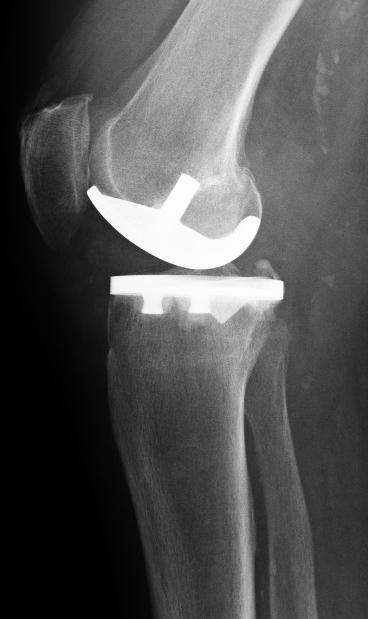

Eine mögliche Behandlung der partiellen Gonarthrose (Kniearthrose) ist der Ersatz der verschlissenen Knorpeloberfläche mit einer Teilprothese (unikondyläre Schlittenprothese).

Die Teilprothese ersetzt die verschlissene Knorpeloberfläche und stellt die schmerzfreie Beweglichkeit des Kniegelenks wieder her.

Die Implantation der lateralen Knieteilprothese erfolgt mittels Knochenzement. Der Arzt befestigt die Bestandteile der Prothese sicher im vorbereiteten Knochenbett. Speziell konstruierte Metall- und Kunststoffmaterialien gewährleisten eine sichere Verankerung und Haltbarkeit der lateralen Knieteilprothese von über 10 Jahren.